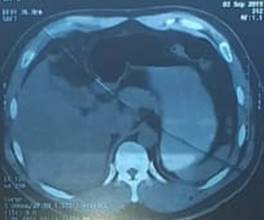

Presentamos el caso de un paciente masculino de 45 años de edad con antecedentes personales de obesidad gradi I, hipertensión arterial en tratamiento con enalapril 10mg y atenolol 25mg al día, dos años de dolor abdominal en hipocondrio derecho sin estudio y cirugía previa por hemorroides.  Acude al servicio de emergencia por presentar hace 24 horas, dolor agudo tipo cólico de moderada a severa intensidad en hipocondrio derecho que se irradia a región lumbar, murphy positivo, y ausencia de signos de irritación peritoneal. El hemograma mostró leucocitos 8.400, neutrófilos 54.3%, úrea: 37,9 creatinina: 1,45, TGO: 42,9  TGP: 57,9 fosfatasa alcalina total: 6,32. La ecografía de ingreso reportó vesícula de paredes engrosadas de 4 mm irregulares de tamaño normal de 47 cc de volumen con cálculos en su interior, el mayor de 15 mm más barro biliar en moderada cantidad, y masa sugestiva de cáncer biliar. (ver figura 1) Se decide el ingreso a hospitalización y se extiende el estudio con tomografía simple trifásica en la cual se observa vesícula bien contraída impresionando en gorro frigio de paredes engrosadas de contenido no valorable por este método. (ver figura 2) Se realizan marcadores tumorales  obteniéndose CA19-9: 0,60 Y Alfafetoproteina: 1,86 dentro de parámetros normales.  Se decide realizar colecistectomía laparoscópica la cual se desarrolla con  tiempo quirúrgico prolongado debido a la obesidad del paciente. Como hallazgo postquirúrgico se encontró vesícula escleroatrófica de 5x3x3 cm de paredes gruesas calcificadas con un lito en su interior, presencia de vasos de neo formación adherida a planos profundos intrahepáticos, con múltiples adherencias hacia epiplón, intestino delgado y colon cístico aumentado de tamaño, colédoco macroscópicamente normal.

Figura 2. Tomografía de abdomen 1